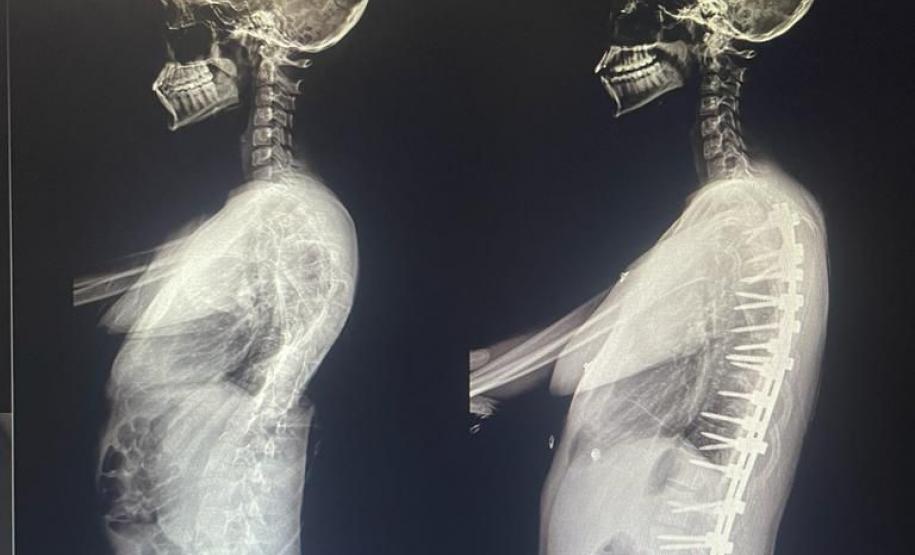

Aos 14 anos, a adolescente Milena de Andrade Carvalho, moradora de Guaratuba, no Litoral do Estado, foi diagnosticada com escoliose idiopática. Sem causa definida, esse tipo de escoliose pode surgir a partir dos quatro anos até a adolescência e ocorre durante o estirão de crescimento. Quando a condição da curvatura ultrapassa os 40 graus, a escoliose se torna progressiva e o paciente continua entortando. Essa condição ocorre com maior frequência em meninas e é muito importante que os pais estejam atentos a qualquer sinal do problema.

“Descobrimos a escoliose por acaso, nunca tínhamos percebido a deformidade, até que um dia ao amarrar meu biquíni, minha mãe observou que eu estava com a coluna torta e ao passar a mão percebeu a curvatura. Decidimos então procurar atendimento médico e tive o diagnóstico da doença já com 50 graus de curvatura e indicação imediata de cirurgia”, contou a adolescente.